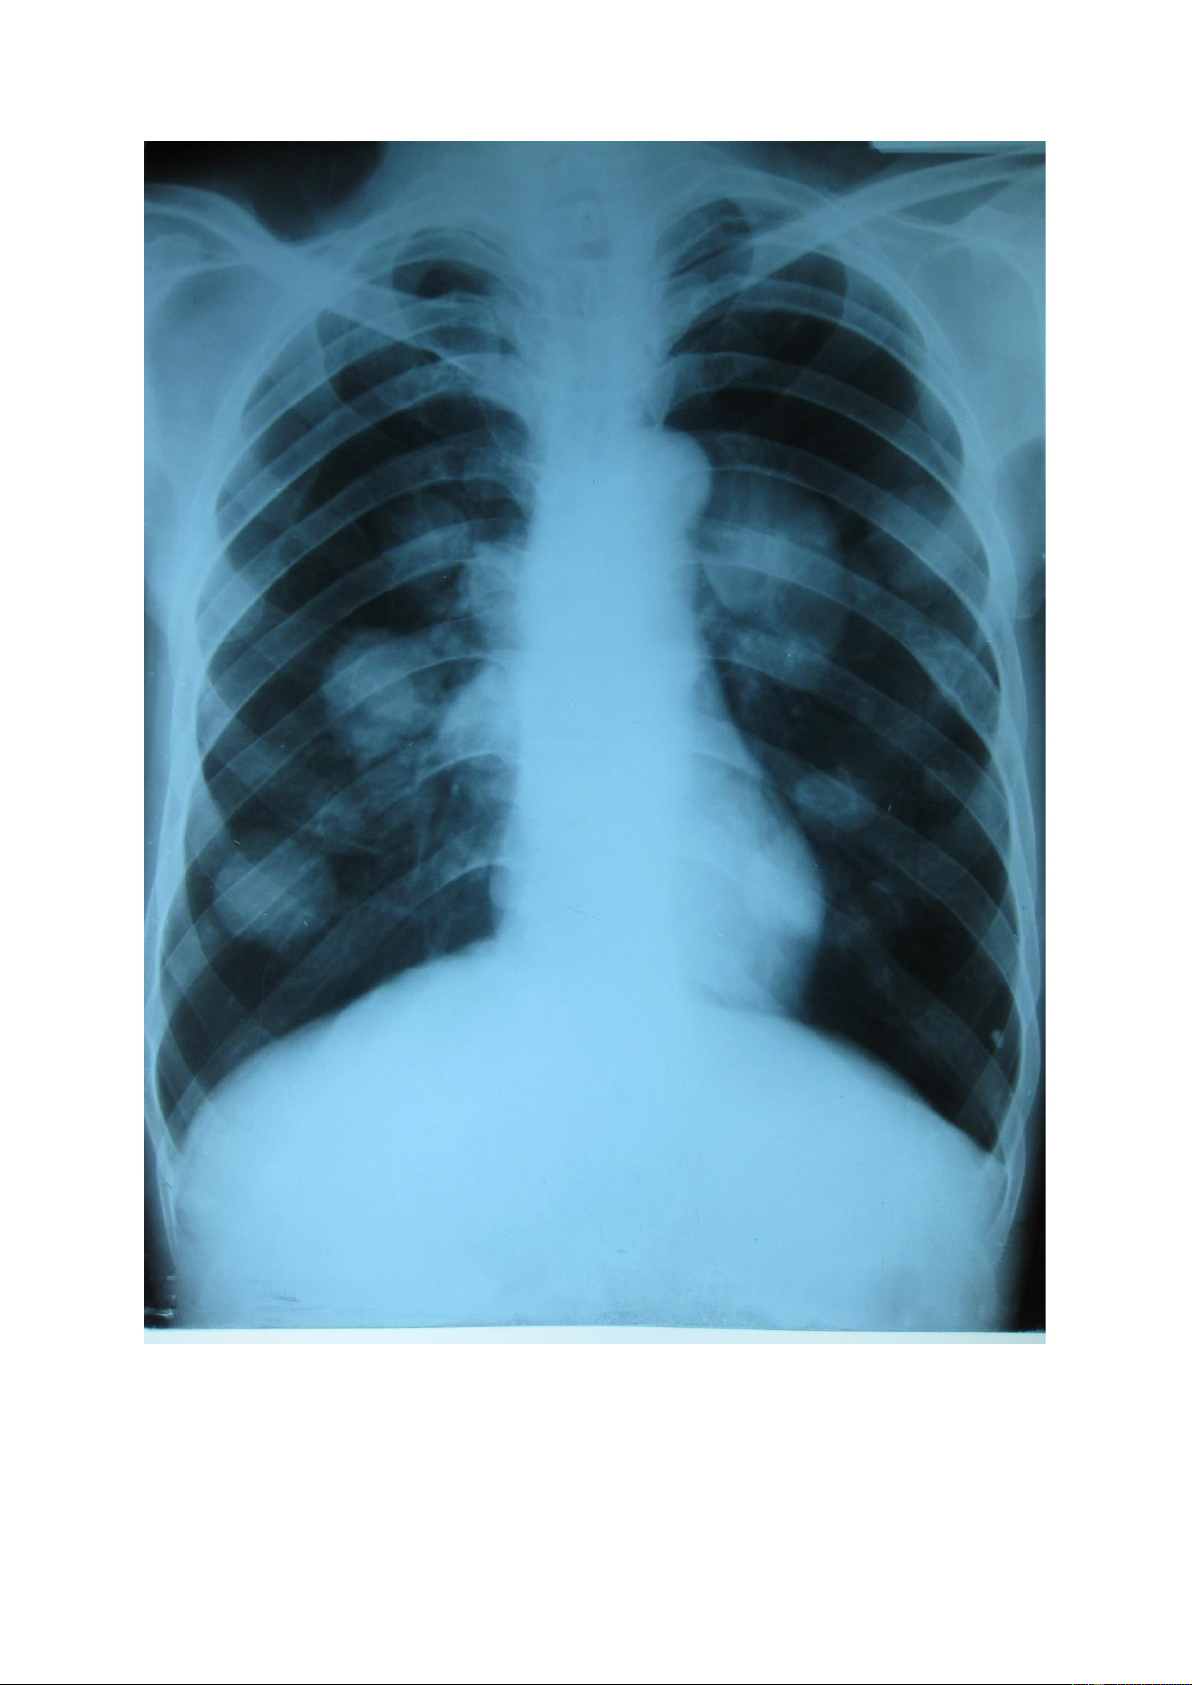

Nốt mờ lớn: là tổn thương có kích thước >3mm và < 3cm, số lượng có thể đơn

độc hoặc nhiều, kích thước có thể đều hoặc không đều, đậm độ cản quang khác nhau. lOMoAR cPSD| 22014077 lOMoAR cPSD| 22014077 1.3.